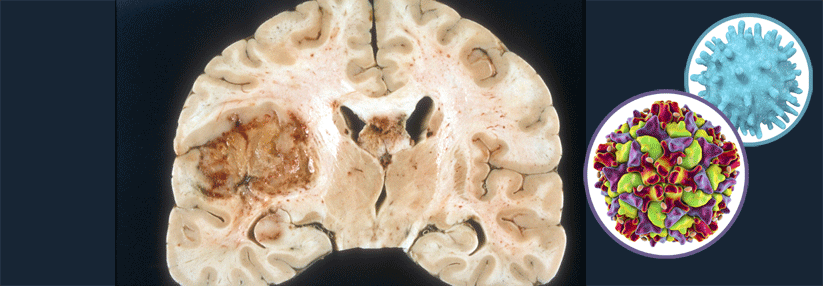

Drei Studien suchen nach den Schwachstellen von ZNS-Tumoren. Drei Studien suchen nach den Schwachstellen von ZNS-Tumoren. © peterschreiber.media – stock.adobe.com

Zielgerichtete Therapien werden mittlerweile bei so einigen Krebserkrankungen erfolgreich eingesetzt. Im Bereich der ZNS-Tumoren ist dies aber noch immer recht schwierig. Dennoch werden auch hier Fortschritte erzielt, wie die Ergebnisse dreier Studien verdeutlichen.